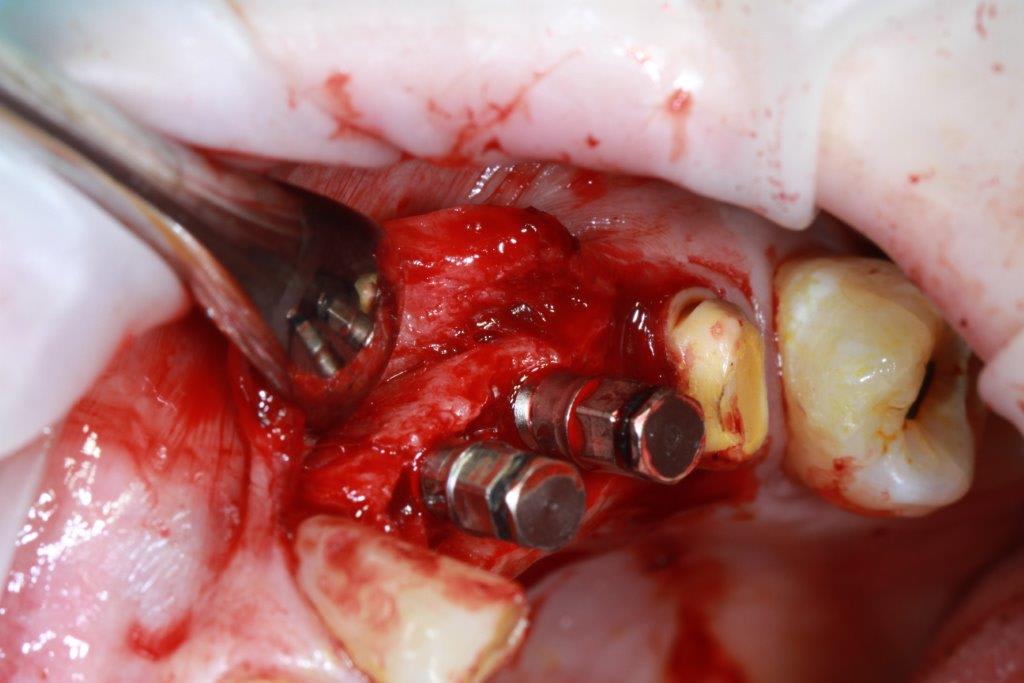

petit cas sympa ancien bridge très mobile....plutôt que d'extraire 25, j'ai déposé la couronne, retraité la dent stabilisation pendant deux mois puis séance d'ostéotension et ce jour pose de deux axioms PX 34120 après expansion...

Pxav, je vois des zones concaves entre les implants et en mesiale, tu laisses les expanseurs pour visser les implants, tu réalises 4 points d'impacte avec les demi-lunes ?

non, uniquement travail par voie crestale, très légère fêlure niveau 23, mais sans conséquence

comme je n'ai pas fait de décharges osseuse en vestibulaire, j'ai effectivement travaillé toute la longueur de la crête, mais, là j'ai ôtè les expanseurs avant de visser les implants car ce sont des PX qui ont un apex assez fin, pour des regular j'aurais pratiqué différemment.

par contre je suis passé par le stade implants lisse (34100 et 34120)

en général (99,9% des cas) je ne constate aucune lyse osseusecrestale, ce type de chir. est très douce pour l'os, lame 15, et ostéotomes, pas de forage, pas de consommation d'os, pas d'agression ni de lavage (piezzo), et je fais toujours attention à laisser du sang (sauf pour les photos) ce qui est le meilleur pansement pour l'os.

par contre les axioms doivent être posé en sous crestal, ce qui est fait ici, avec sans doute comme souvent une nécessitè d’ostéotomie, lors de la mise en charge, car il est fréquent que le col implantaire soit recouvert.